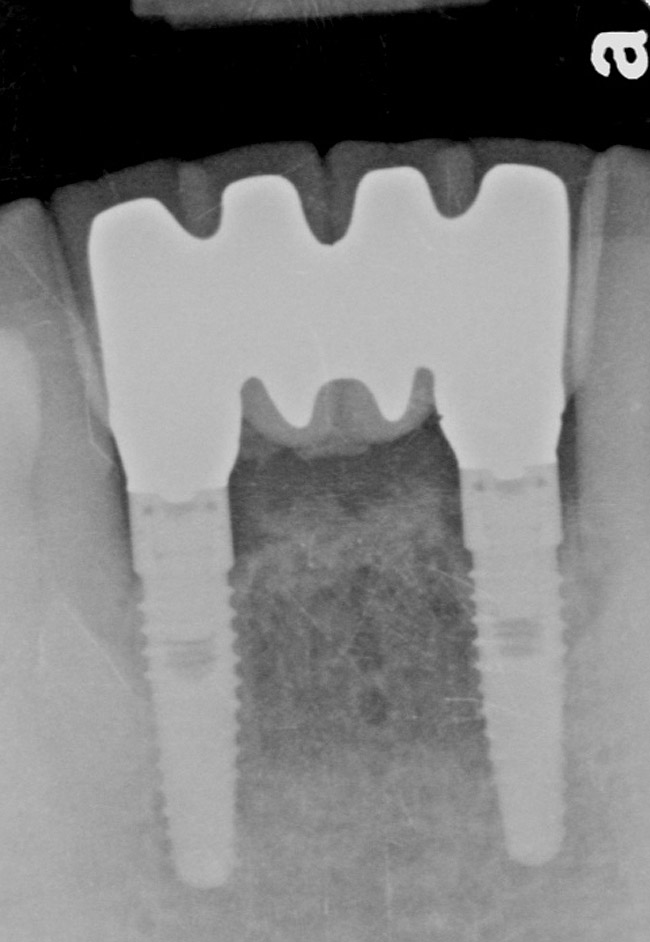

Figure 9  The 4-year postoperative radiograph.

Figure 9

The patient was given postoperative instructions and advised to maintain a soft diet for 6 to 8 weeks to protect the implants. The patient was followed weekly for the first 3 weeks and monthly thereafter. After 4 months of healing, the provisional restoration was removed and the soft tissues were examined. Mature, keratinized gingival tissues were present facially, lingually, and interproximally. Nonkeratinized tissue could be seen at the tissue surfaces of the ovate pontics and in the intrasulcular regions of the implant abutment units. No clinical probing depths beyond 1 mm were found adjacent to the abutments. The healed tissue represented an acceptable clinical result especially in light of the gap that had been present at the time of implant placement (Figure 7A and Figure 7B). Final impressions were made, and the permanent ceramo-metal screw-retained prosthesis was placed within 8 weeks (Figure 8).

This patient has been followed for 4 years with no complications and no discernable clinical changes in soft- or hard-tissue levels.